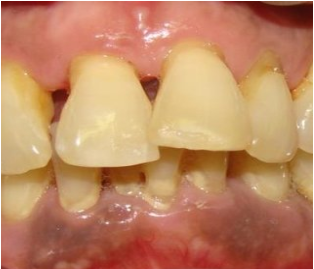

Penderita periodontitis agresif biasanya tidak menunjukkan gejala atau tanda-tanda dari penyakit sistemik. Untuk gejala yang biasanya ditemukan pada kasus pasien dengan periodontits agresif antara lain kegoyangan gigi pada gigi molar pertama (gigi geraham besar pertama), serta nyeri saat ada tekanan / mengunyah yang biasanya tidak berlangsung lama. Pada kasus yang parah biasanya muncul infeksi bernanah pada gusi (pembengkakan pada gusi) dan gusi berdarah.

Untuk mendiagnosis periodontitis akut / periodontitis agresif, sebelumnya dokter gigi akan melakukan anamnesa (tanya jawab) kepada pasien terkait keluhan yang dirasakan dan riwayat kesehatan pasien. Selanjutnya dokter gigi akan memeriksa apakah ada perdarahan disekitar gigi akibat plak, dan juga dokter akan mengukur kedalaman dari poket (celah antara gusi dan gigi). Dari gambaran klinis biasanya gusi terlihat turun.  Selain itu bisa juga dilakukan pemeriksaan penunjang untuk menegakkan diagnosa dengan menggunakan pemeriksaan foto rontgen panoramik untuk mengetahui pola kerusakan dari tulang di sekitar gigi, untuk membedakannya dengan periodontitis kronis ataupun penyakit periodontal lainnya. Pola kerusakan tulang di sekitar gigi pada periodontitis agresif berbentuk putaran atau bisa vertikal.